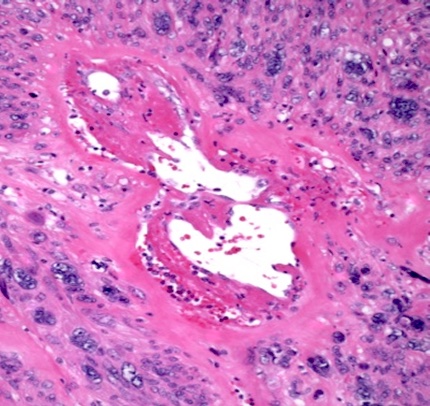

Microscopic (histologic) description

- Leiomyoma with bizarre nuclei:

- Bizarrely shaped, hyperchromatic, multilobulated nuclei with nuclear pseudoinclusions

- Arranged in a multifocal to diffuse distribution in a background of a typical leiomyoma (Am J Surg Pathol 2014;38:1330, Mod Pathol 2017;30:1476, Am J Surg Pathol 2016;40:923, Cancer 2014;120:3165, Am J Surg Pathol 1997;21:1261)

- Alveolar edema, staghorn vessels

- Low mitotic activity (< 5 mitoses/10 high power fields)

- Absence of tumor cell necrosis

- Vasculature variable (staghorn vessels, thick walled vessels, fibrinoid necrosis of vessel walls, luminal vascular obliteration)

- Diagnostic key: intermixed normal spindled smooth muscle cells

Microscopic (histologic) images

Contributed by Sabrina Croce, M.D., Ph.D., Kristina Doytcheva, M.D., Jennifer A. Bennett, M.D. (Case #508) and @Andrew_Fltv on Twitter